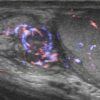

Viêm mào tinh hoàn

» Thông tin: Nam giới – 39 tuổi.

» Lâm sàng: Sưng đau vùng bìu.

# Viêm mào tinh hoàn apxe hóa.